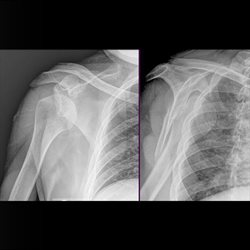

Various adult extremity cases. Shoulder, wrist, ankle, elbow.